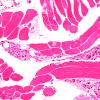

PERIPHERAL NEUROPATHY

11 VASCULITIS - VASCULOPATHY

2 Vasculopathy (3)